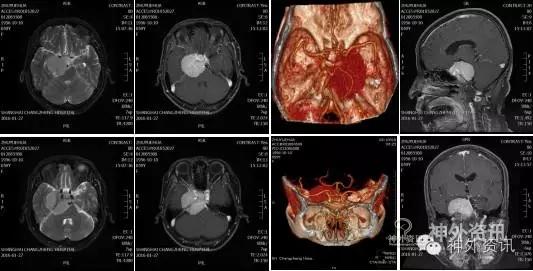

神经系统检查未见明显阳性体征。MRI、CT、CTA及三维重建显示鞍旁见4.7cm不规则信号影,病灶跨颅中、后窝,推挤并包绕右侧颈内动脉及分支、大脑后动脉和基底动脉及分支,MRI显示T1呈等信号影,T2呈高信号影,FLAIR呈高信号,DWI未见异常高信号;增强后均匀强化,可见脑膜鼠尾征;脑干受压明显。

诊断:右侧蝶岩斜区巨大脑膜瘤(以上斜坡为主,侵犯同侧海绵窦后部)。术前详细计划后选择改良的Kawase入路切除肿瘤。

术前影像学资料